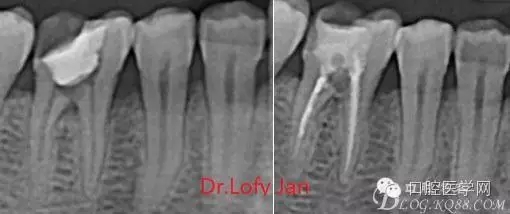

根管治療術(shù)是牙體牙髓疾病治療中最復(fù)雜和最關(guān)鍵的治療項(xiàng)目。根管充填材料抵達(dá)根尖、并能嚴(yán)密堵塞根尖孔,是確保根管治療效果的關(guān)鍵指標(biāo)。為了保證根管充填到位,醫(yī)生需要在術(shù)前照牙片以了解牙根根管的數(shù)量、彎曲程度和長度,在術(shù)中有時(shí)需要插針照牙片來精確測量根管長度,術(shù)后必須照牙片以確定是否根管充填到位,如果欠填或超填,就需要重新充填、重新照牙片確認(rèn),直到根管充填到位。所以,在患者接受根管治療時(shí)有時(shí)會反復(fù)照牙片。

《數(shù)字化根尖片、曲面斷層片、CBCT測量牙齒長度準(zhǔn)確性的比較研究》文中顯示:平行投照數(shù)字化根尖片影像長度和牙齒實(shí)際長度之間無顯著性差異(P0.05);數(shù)字化曲面斷層片影像長度和牙齒實(shí)際長度之間有顯著性差異(P0.05),平均失真率為17.05%。CBCT冠狀面測量結(jié)果中除上頜前磨牙區(qū)、下頜前磨牙區(qū)與真實(shí)長度差異無統(tǒng)計(jì)學(xué)意義(P0.05)外,其余6個(gè)分區(qū)差異均有統(tǒng)計(jì)學(xué)意義(P0.05);矢狀面測量結(jié)果中上頜磨牙區(qū)、下頜磨牙區(qū)、下頜前磨牙區(qū)、下頜尖牙區(qū)、下頜前牙區(qū)與真實(shí)長度比較差異均有統(tǒng)計(jì)學(xué)意義(P0.05)。結(jié)論平行投照數(shù)字化根尖片較曲面斷層片和CBCT能更加精確地反映牙齒的真實(shí)長度。

病例分析:曲面斷層片在x線輔助診斷與檢查中目前大多數(shù)文獻(xiàn)和著作都建議只能作為初診拍片檢查手段,不能作為終末疾病的確診與手術(shù)療效的評價(jià)指標(biāo),臨床大部分中小型門診都因?yàn)樵O(shè)備不齊全導(dǎo)致信息偏差很大。